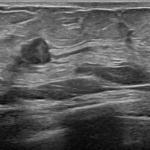

マンモグラフィ・超音波(エコー)

腫瘍の場所や大きさ、乳管の拡張具合を確認します。小さすぎる場合は写らないこともあります。